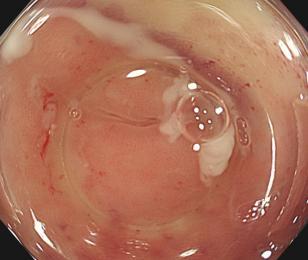

• EyeMax洞察胆胰管成像系统辅助内镜逆行阑尾炎治疗术的疗效及安全性分析

摘要:目的 探究一次性eyeMax洞察胰胆管成像系统辅助内镜逆行阑尾炎治疗术(ERAT)治疗阑尾炎的效果及安全性。方法 回顾性分析2023年4月-2024年9月在该院就诊,通过影像学或内镜检查确诊的54例非复杂性阑尾炎患者的临床资料。所有患者均行eyeMax洞察胆胰管成像系统辅助ERAT,于直视下观察阑尾腔,并通过冲洗、取石、扩张狭窄和支架引流等措施治疗阑尾炎。观察手术相关指标、术后疼痛程度、并发症发生情况、术后1年内复发率、结肠镜下表现、胰胆管成像系统下表现和胆胰管成像系统下治疗情况。结果 54例患者均顺利完成手术,技术成功率为100.0%,手术时间(60.6±27.9)min,住院时间(3.6±1.5)d;30例(55.6%)阑尾开口及周边黏膜充血水肿,2例(3.7%)可见脓液及污秽物流出;54例(100.0%)患者阑尾腔内壁充血水肿,51例(94.4%)可见腔内絮状物、脓液或脓苔附着,25例(46.3%)可见腔内粪石,15例(27.8%)可见管腔走形迂曲或狭窄。所有患者予以eyeMax洞察胰胆管成像系统治疗,简单灌洗54例,网篮取石20例,支架引流25例。术后VAS评分为0(0,0)分,明显低于术前的6(3,7)分,手术前后比较,差异有统计学意义(Z = -6.24,P = 0.000)。所有患者术后症状均暂时缓解,术中及术后未发生穿孔和大出血等严重不良事件。随访1年内,阑尾炎复发率为20.4%(11/54)。结论 EyeMax洞察胆胰管成像系统辅助ERAT是治疗非复杂性阑尾炎安全和有效的疗法,其具有直视下精准操作、保留阑尾功能、症状快速缓解、无X线暴露和精准诊疗阑尾病变等优势。值得应用于临床。